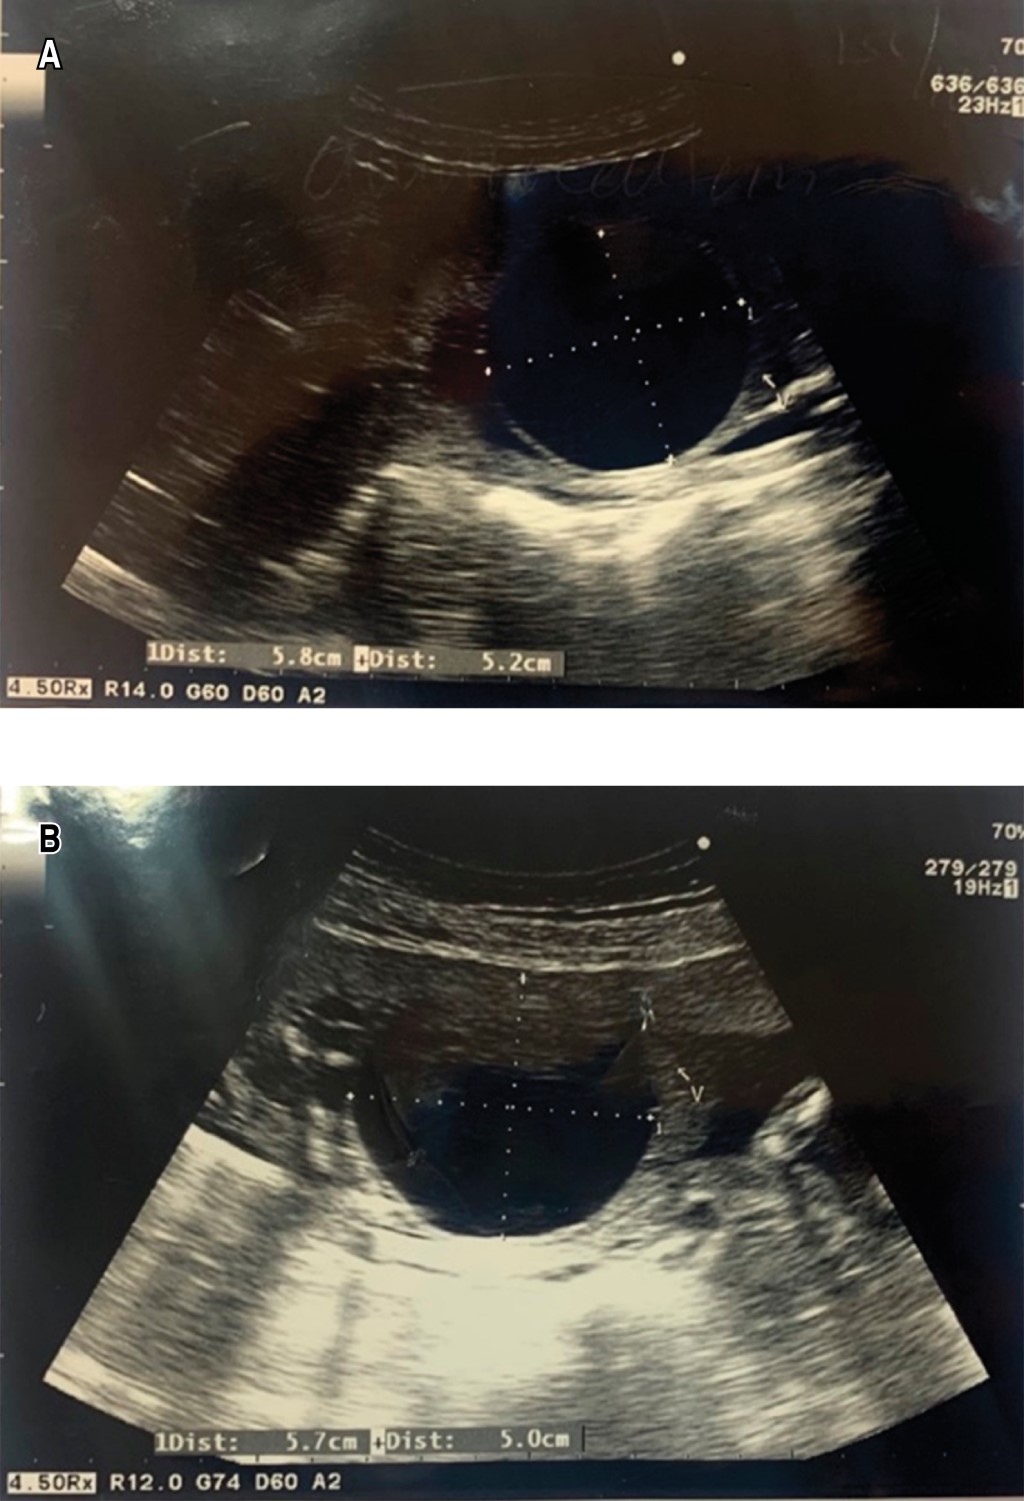

Paciente primigesta de 29 años, con hipotiroidismo controlado como único antecedente médico de importancia. Refiere haber recibido adecuado control prenatal, con ingesta de multivitamínicos, ácido fólico y ácido acetilsalicílico 100 mg desde inicios tempranos de la gestación. Asimismo, se diagnosticó diabetes gestacional a las 25 semanas de gestación, la cual se manejó con tratamiento nutricional. Se le realiza ultrasonido a las 12.5 semanas de gestación de primer trimestre reportando tamaño vesical de 9.4 mm (arriba de lo esperado) (Figura 1), con dilatación pielocalicial en ambos riñones. A las 16 semanas de gestación acude a control donde se diagnostica obstrucción urinaria baja con megavejiga fetal de 5.7 × 5.8 × 5.2 cm (Figura 2), motivo por el cual se envía a cirugía fetal para tratamiento. Se realiza amniocentesis con reporte de cariotipo 46 XY, sin anormalidades numéricas ni estructurales.

Figura 2